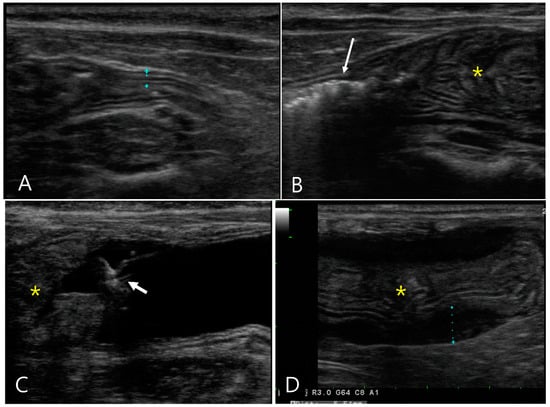

2.3. Case 3